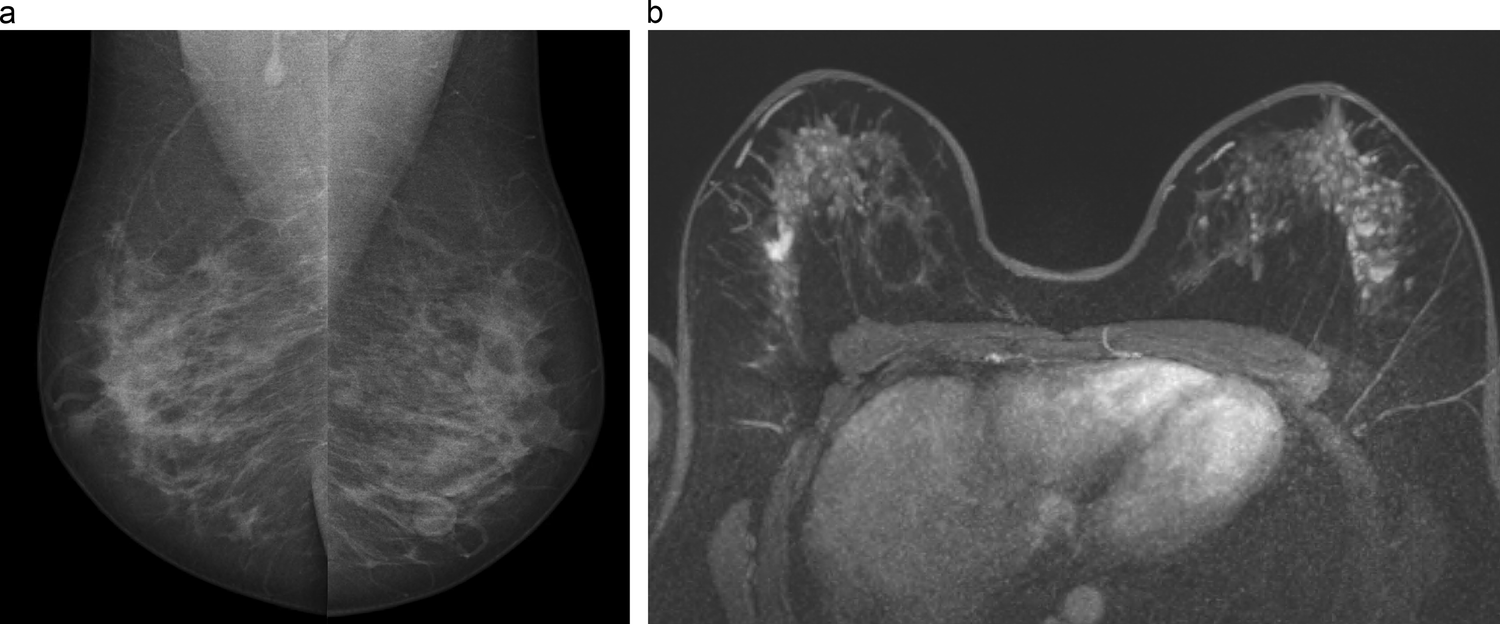

Fig. 4

46-year-old patient with a prior history of chest irradiation for Ewing sarcoma. Screening examinations. MLO views (a) from mammography examination that was deeemed normal. Contrast-enhanced breast MRI (b) reveals bilateral breast abnormalities. In the right breast, an irregular spiculated mass is visible, corresponding to a 13 mm NST carcinoma. In the left breast, segmental heterogeneous nonmass enhancement is seen, corresponding to extensive DCIS with microinvasion